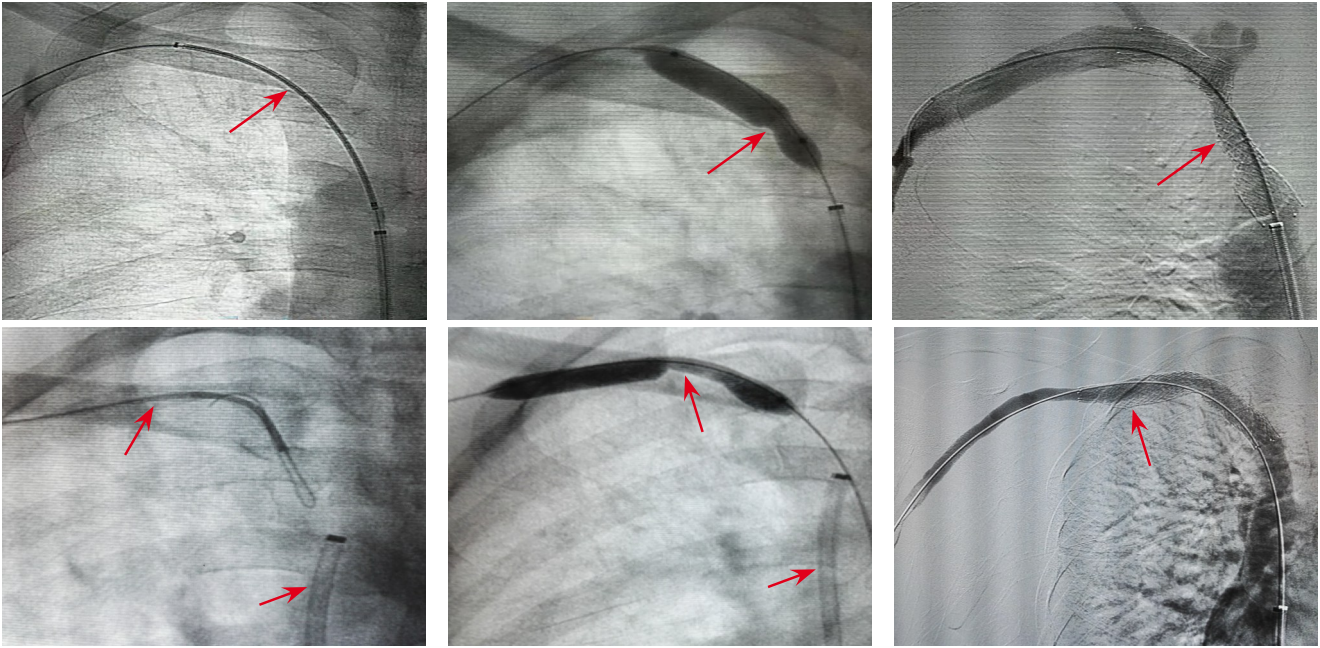

背景与目的 胆道感染是恶性胆道梗阻介入治疗后的常见并发症之一,但目前缺乏有效的早期预测指标。本研究探讨Toll样受体2(TLR2)mRNA、组氨酸脱羧酶(HDC)及中性粒细胞CD64在恶性胆道梗阻患者数字减影血管造影(DSA)引导胆道支架联合放射性粒子链植入术后胆道感染的表达变化及其预测价值。方法 回顾性纳入2021年1月—2024年2月河北省邢台市人民医院285例接受DSA引导胆道支架联合放射性粒子链植入术的恶性胆道梗阻患者,根据术后是否发生胆道感染分为感染组(46例)和未感染组(239例)。比较两组基线资料及术前、术后1 d炎症指标[C-反应蛋白(CRP)、降钙素原(PCT)、白细胞]及TLR2 mRNA、HDC、CD64水平。采用Pearson相关分析,评价其与CRP的相关性,采用多因素Logistic回归分析影响因素,并通过受试者工作特征曲线(ROC)评估其预测价值。另纳入2024年3月—2024年10月50例患者进行前瞻性验证。结果 感染组糖尿病、胆结石及高位梗阻比例高于未感染组(均P<0.05)。术后1 d感染组CRP、TLR2 mRNA、HDC及CD64水平均高于未感染组(均P<0.05)。TLR2 mRNA、HDC及CD64与CRP水平均呈正相关(r=0.729、0.682、0.755,均P<0.05),并与感染严重程度呈正相关。多因素Logistic回归分析显示,校正糖尿病、胆结石及梗阻类型后,TLR2 mRNA、HDC及CD64仍为术后胆道感染的独立相关因素(均P<0.05)。ROC分析显示三者联合预测术后胆道感染的曲线下面积为0.923,敏感度为89.13%,特异度为84.10%,优于单项指标。前瞻性验证结果显示预测模型与实际结果一致性良好(κ=0.864)。结论 恶性胆道梗阻患者DSA引导胆道支架联合放射性粒子链植入术后TLR2 mRNA、HDC及CD64水平升高与胆道感染发生相关,三者联合检测具有较高的早期预测价值,可为术后胆道感染的早期识别提供参考。